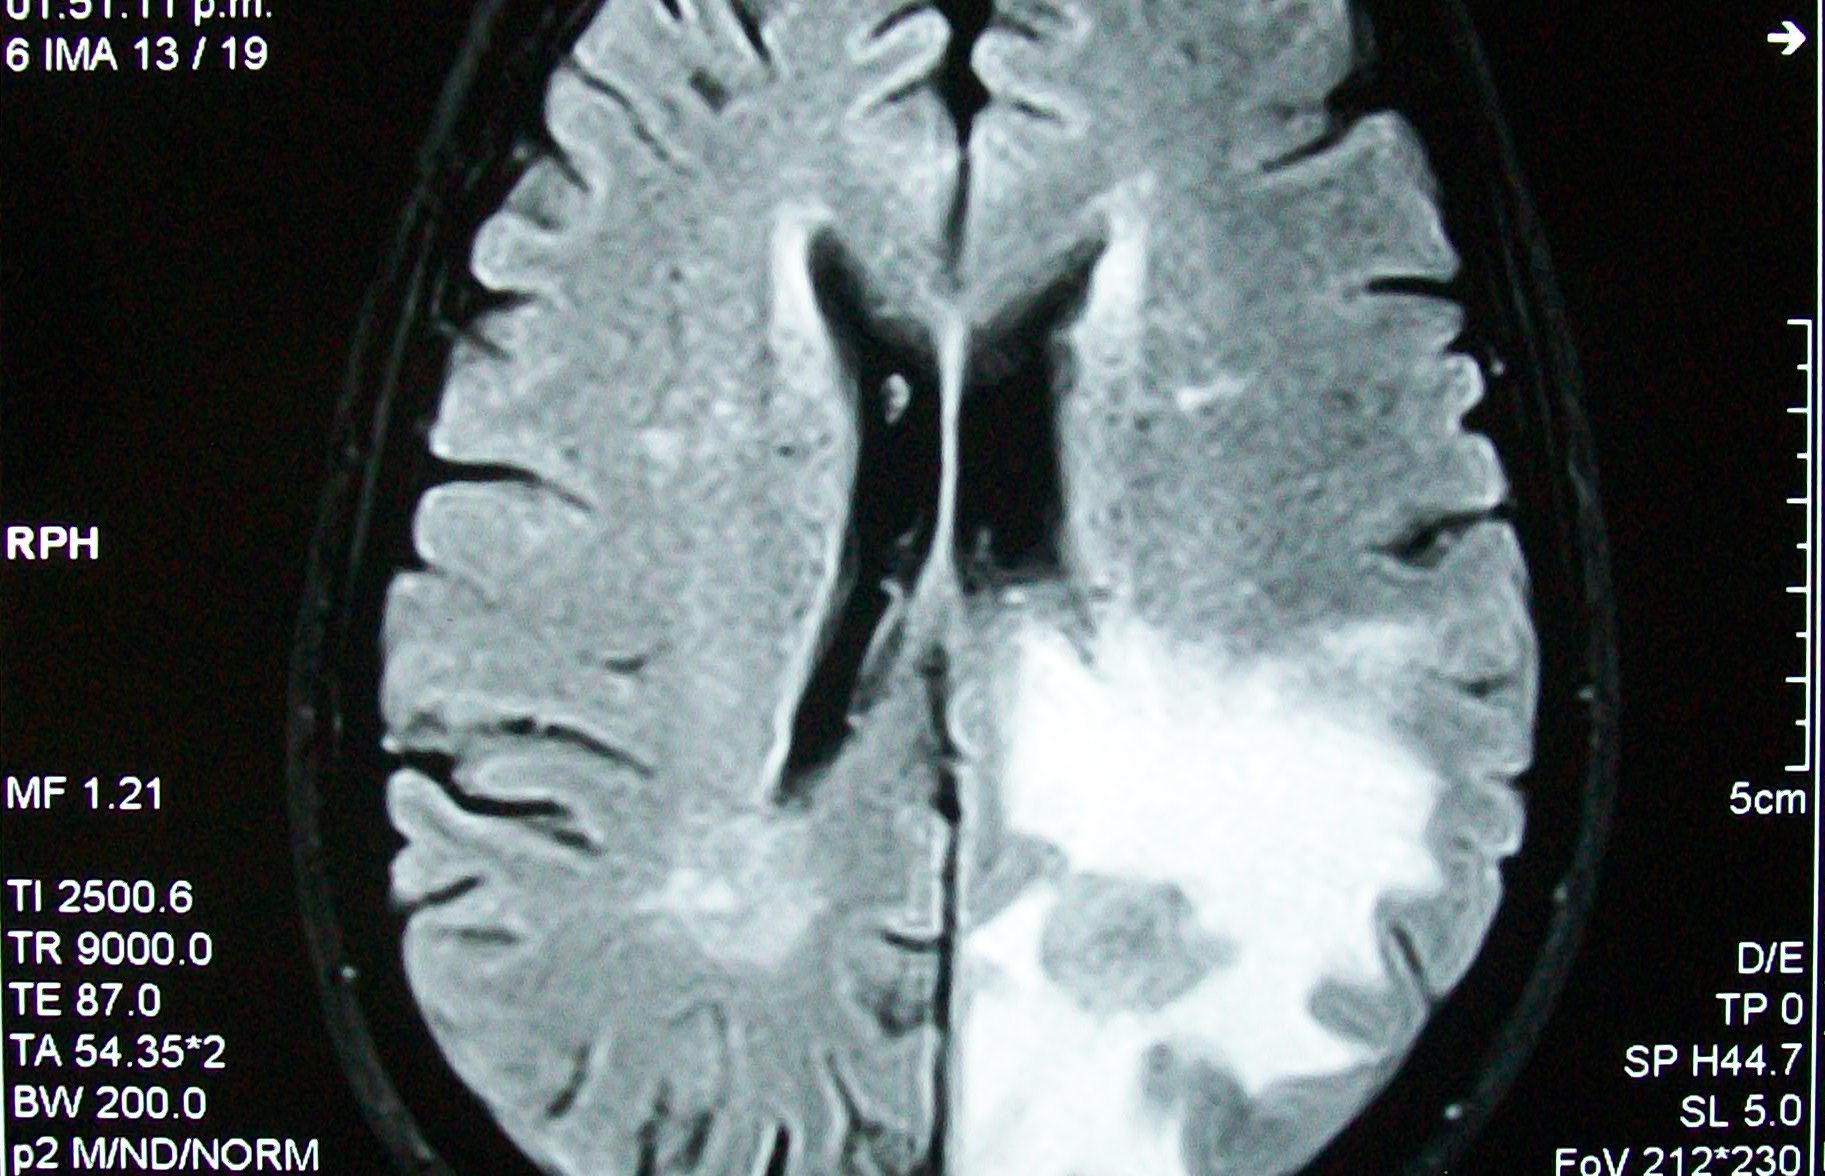

Beyin tümörü uyku hali. Yetişkinlerde ikincil beyin tümörleri birincil beyin tümörlerinden çok daha yaygındır. Ancak şikayetler çok daha çeşitlilik gösterebilir. 1925 yılından beri bilinen bu beyincik tümörü çok ayrı hücresel ve klinik özellikeri olan ve oldukça habis karekterli bir beyincik tümör tipidir beyinciğin çocuklarda en sık tümörü olup tüm primer beyin tümörlerininin 4 10 teşkil ederler. Patoloji alındı ondada tam teşhis konulmadı.

Sürekli uyku hali i̇çin hangi doktora gidilmeli. Eşim iki ay önce beyin tümörü teşhisi kondu. çekilen emar ve tomografi sonucuna göre tümör dendi. Bu şikayetler beyin tümörü belirtisi olabilir.

Uykuyu kontrol eden sinirler beyin sisteminde yer aldığı için sürekli uyku problemini çözmek için nöroloji bölümüne gitmeniz gereklidir. İkincil beyin tümörleri en sık kanser öyküsü olan kişilerde görülür. Denge kaybı uyku hali gözde görme sorunları duyma sorunları el ya da ayaklarda his sorunları ruhsal değişiklikler halüsinasyonlar görebilir yemek yeme sorunları yutkunma sorunları yemek yeme sorunları halsizlik trombosit düşüklüğü lökosit. Sadece uyku hali be yorgunluğu vardı.

Nöbet geçirmesi şimdiye kadar olmadı. Uyku apnesi bulunanların kalp damar hastalıklarına ve beyin damar hastalıklarına inme gibi yakalanma riski daha yüksektir. Ancak baş ağrısı bazen beyin tümörü beyin kanaması ve anevrizma gibi yaşamı tehdit eden. Ancak nadir durumlarda metastatik beyin tümörü vücudunuzun başka yerlerinde başlayan kanserin ilk belirtisi olabilir.